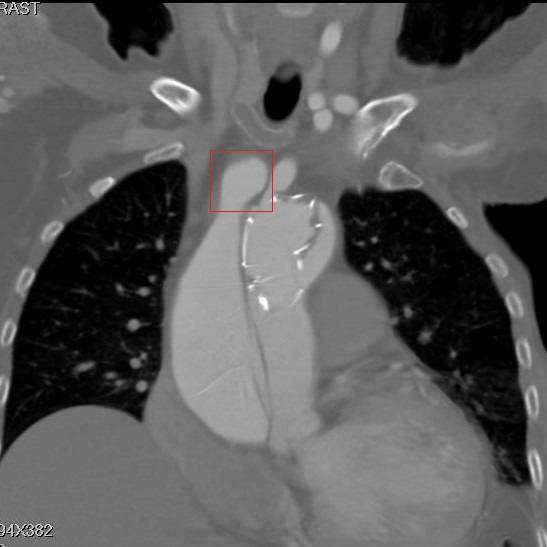

患者是一例A型主动脉夹层,上图中F示假腔,T示真腔,这没什么奇怪。但仔细一看,胸骨的边缘具有高密度影,中间还有一小片低密度区,这例病例接受过前胸正中开胸的手术。

冠状面重建,方框示头臂干看上去完全开口于假腔,左颈总似乎被支架盖住了